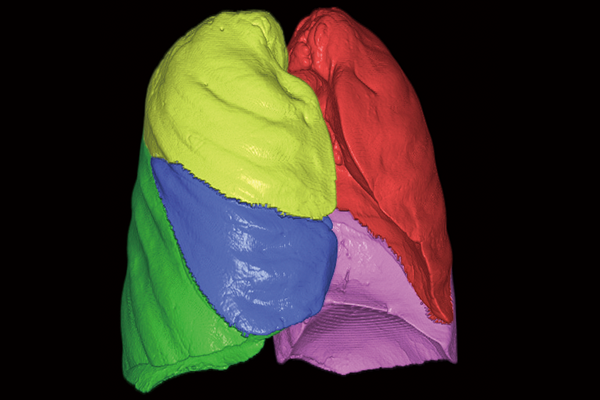

肺葉

肺解析